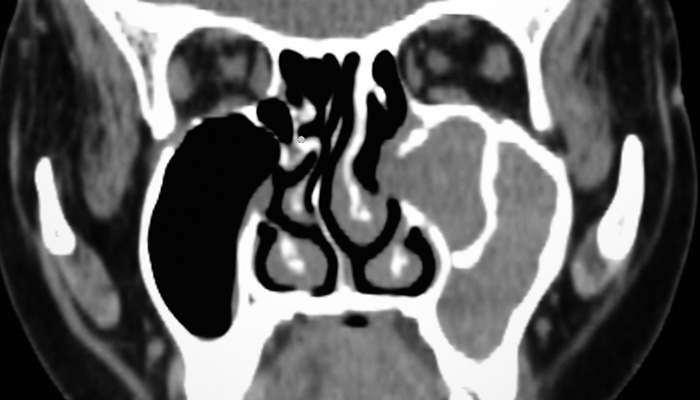

The Brigham and Women’s Hospital Multidisciplinary Sinus Group is a research and patient-care team focused on the diagnosis and treatment of sinus disease. Our multidisciplinary team is made up of allergists, ENT surgeons, and research scientists who work towards the common goal of understanding and managing chronic sinus disease